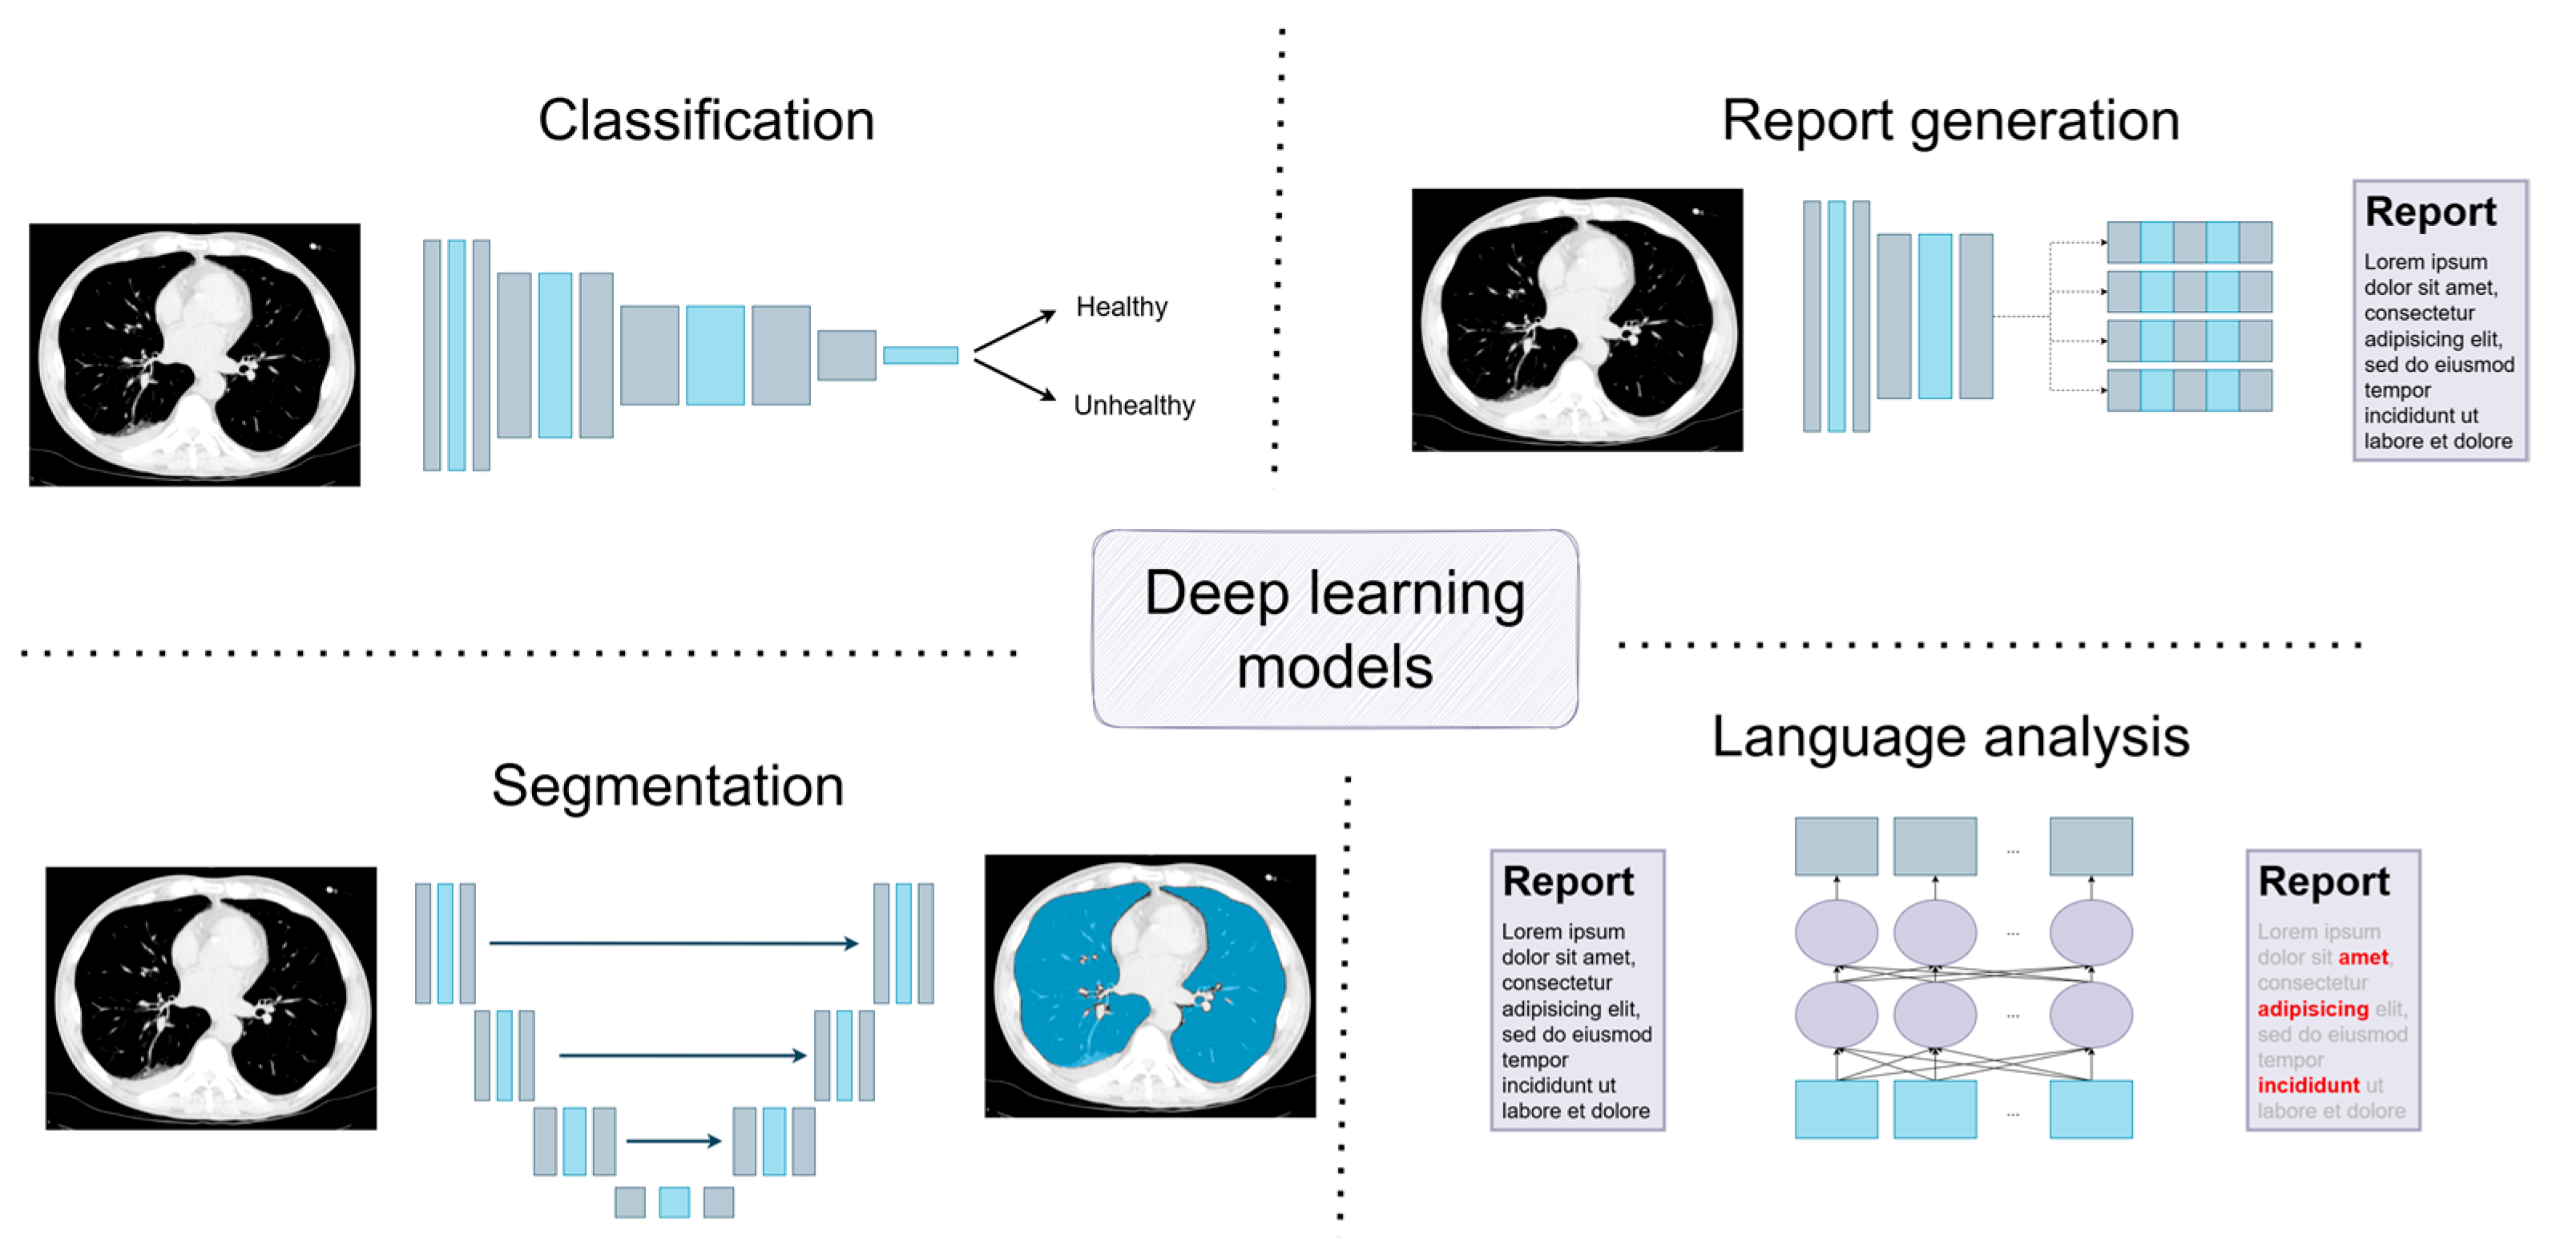

3. Deep Learning Models: A Short Introduction to Current Solutions

3.1. Classification

3.2. Segmentation

3.3. Report Generation

3.4. Language Analysis